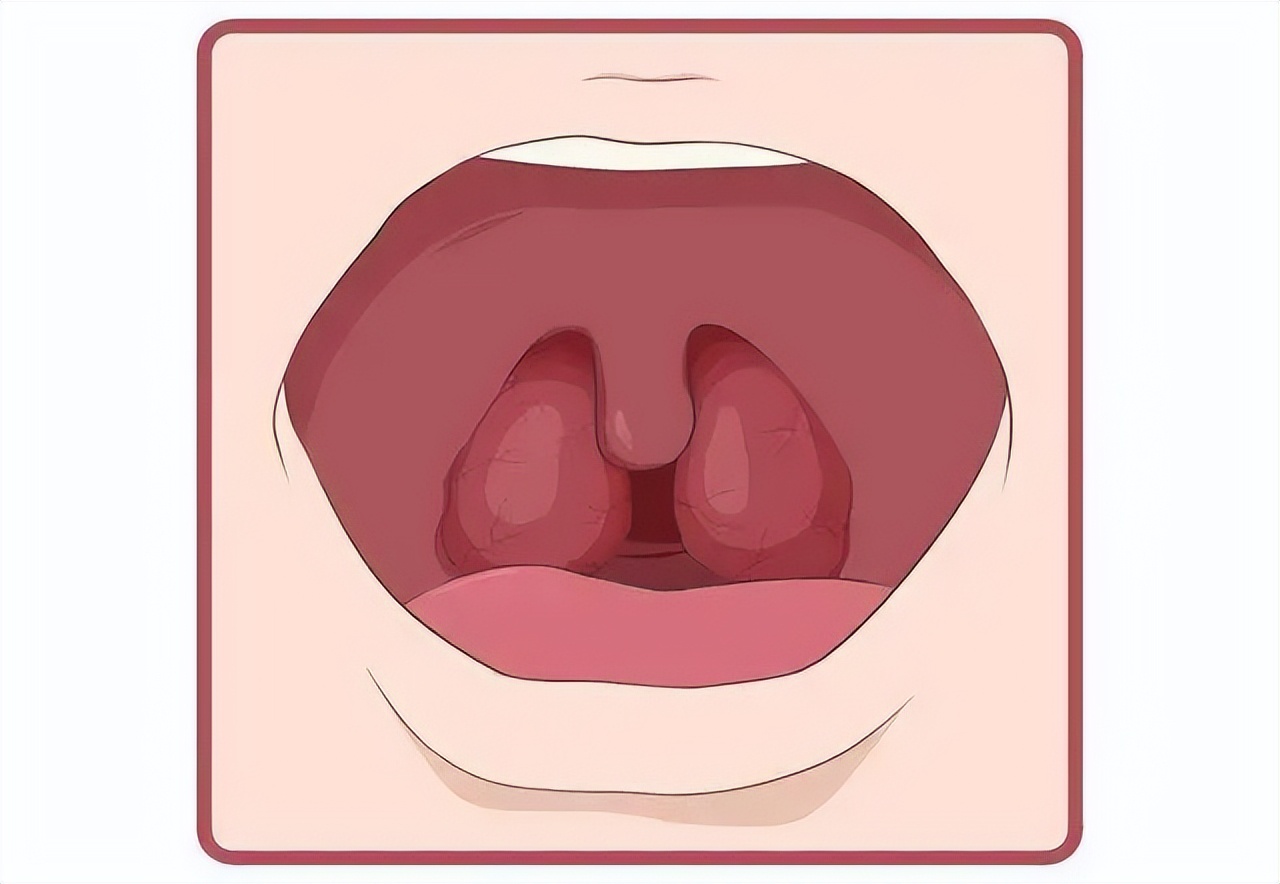

扁桃体是什么?在哪里?

扁桃体位于消化道和呼吸道的交会处,此处的粘膜内含有大量淋巴组织,是经常接触抗原引起局部免疫应答的部位。实际上扁桃体是人体的淋巴器官,健康的扁桃体是人体的“守卫”,按照结构分类,扁桃体可以分为三类:腭扁桃体、咽扁桃体(又称腺样体)、舌扁桃体。